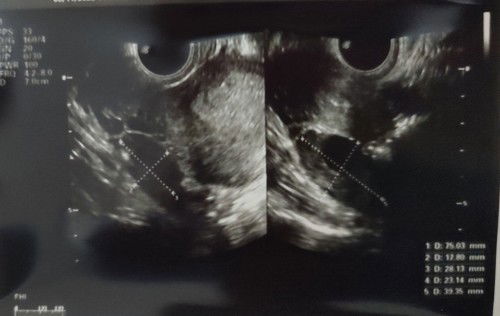

Nyambung dari postingan aku sebelumnya tentang keluhan uk 6w sempat kram, flek, lalu sperti haid lagi. Lalu dicek ke obgyn. Qadarullah, kata beliau rahim saya sudah bersih, keluar bareng dengan pendarahannya. Untungnya tdk bahaya hanya perlu minum antibiotik & tidak perlu dikuret. Ada yg pernah ngalamin ga bun? Biasanya bisa hamil lagi rentang waktu brp lama ya? Maklum pertama hehe😅 #pejuang_garisDua #seriusnanya #ingintahu